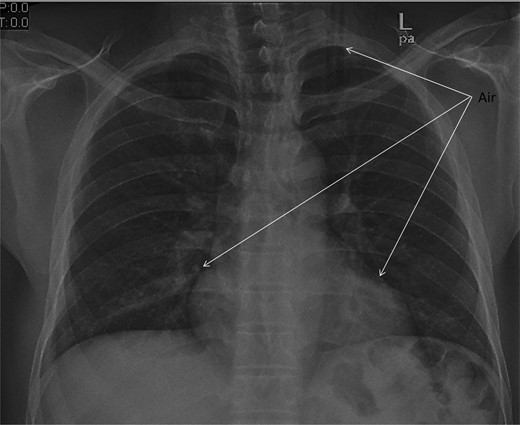

Chest X-ray and head, neck and chest computed tomography (CT) confirmed the diagnosis and extension of PM (Figs 1–3). CT revealed fracture of the floor of left orbit with soft tissue, fat herniation into left maxillary sinus roof, left orbital emphysema with no muscular entrapment. Gas was observed in periorbital tissues, left temporal scalp, infratemporal fossa, left parapharyngeal space and left cheek. Moreover, tissue planes in the neck revealed the presence of air particularly around the carotid vessels, in the posterior triangle and superior mediastinum (PM) around the thymus, trachea (middle), left side of the aorta and anterior to the sternum. However, on auscultation, lungs were clear with and the laryngeal passages and trachea looked normal.

CT scan shows the extension of air from the face, neck and chest.